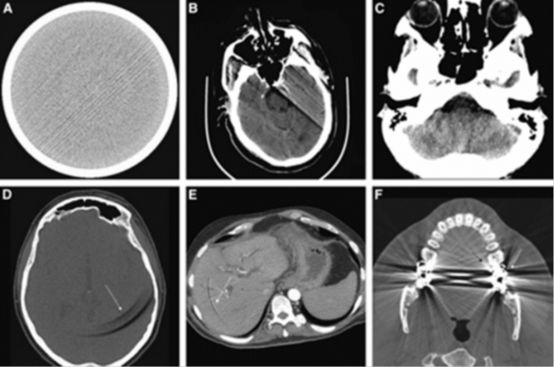

35.電腦斷層影像中,箭號所指屬於下列何種假影?

(A)motion artifacts

(B)metal artifacts

(C)truncation artifacts

(D)partial-volume artifacts

假影(Artifact)

(1)Motionnartifact

病人移動造成偏移,使得重建後的影像出現帶狀假影

(2)Metalnartifact

金屬導致某些部分衰減較強,影像呈現較白,主要是產生散射狀的條紋假影

(streaknartifact)。*以內差法補足

(3)Beam-hardeningnartifacts

衰減後光子的平均能量上升,使得影像上像素內的實際灰階值比影像中灰階值大,影像較白。

(4)Ringnartifacts

第三代CT中,有一個Detector壞掉或是需要重新校準,會在各個角度提供錯誤的讀值,造成環狀的假影

(5)Partialnvolume artifacts

由於射束的發散,使得額外的組織被暫時涵蓋,造成Detector偵測上的不連續,影像上出現陰影假影(Bloomnartifact)

* Pixel越小則此效應越低=thinnslice, small FOV, large matrix

*使密度差別較大的物體邊緣變模糊

*SpiralnCT可以減少部分體積效應

(6) conenbeam artifact

由於錐形的幾何關係,使射束呈發射狀,使得射束中間的X光垂直掃描軸(Z axis),但偏射束外側的X光卻不垂直於掃描軸即落於影像平面(imagenplane)之外。其假影嚴重程度與射束發散的程度和slice collimation有關。

(A)motion artifacts 運動假影

(B)metal artifacts 金屬假影

(C)truncation artifacts 截斷假影

(D)partial-volume artifacts 部分體積假影